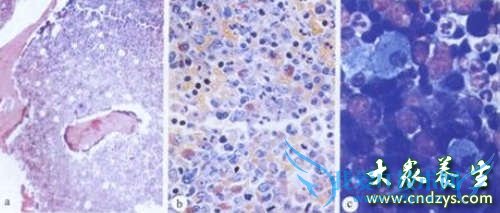

碱性磷酸酶是诊断胆道系统疾病时常用的指标.碱性磷酸酶存在于机体的各个组织,以骨骼,肝脏,肾脏含量较多.正常血清中的碱性磷酸酶主要来自于骨骼,由成骨细胞产生,经血液到肝脏,从胆道系统排泄.胆汁淤积性肝炎肝炎和肝外梗阻时此酶明显升高,ALP只能提示胆道梗阻性病变,不能鉴别梗阻是良性还是恶性.一般慢肝大多都有多多少少的纤维化现象,只是轻重而已.

碱性磷酸酶偏高预示着肝脏异常,碱性磷酸酶偏高时,有可能是肝囊肿、肝结核、阻塞性黄疸、继发性肝癌和原发性肝癌等;碱性磷酸酶偏高预示着骨骼疾病,碱性磷酸酶偏高时,有可能是骨软化症、骨折愈合期、骨细胞癌和恶性肿瘤骨转移等;碱性磷酸酶偏高预示着白血病、甲状腺机能亢进。